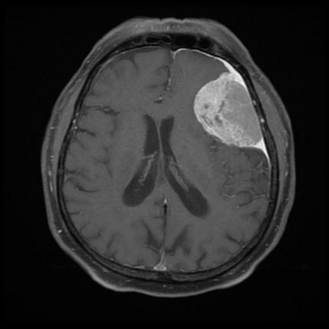

A 19‑year‑old college student presents with sudden‑onset fever, headache, vomiting, and a rapidly spreading purpuric rash. He appears confused, and his BP is measured to be 80/50 mmHg, HR 120/min, and Temp 39.5°C. On examination, he has petechiae and purpura over his lower limbs and trunk. He succumbs to his illness, and an autopsy is carried out. The gross specimen of the brain is shown below. Which of the following pathogens is the most likely cause of his condition?

Options:

A) Streptococcus pneumoniae

B) Haemophilus influenzae type B

C) Neisseria meningitidis

D) Listeria monocytogenes

Correct answer: C) Neisseria meningitidis